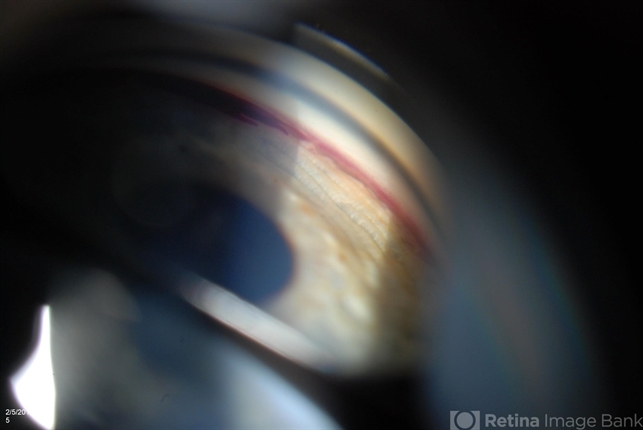

- gonioscopy, angle recession

- Jason S. Calhoun, Department of Ophthalmology, Mayo Clinic Jacksonville, Florida

- Photo slit lamp biomicroscope

- Patient with blunt trauma to the right eye due to a BB gun incident. Patient was present with a hyphema at 8-o'clock about 1mm thick. Gonioscopy photos were then taken to show blood from the hyphema entered into the anterior chamber. Patient had no angle recession in the right eye.